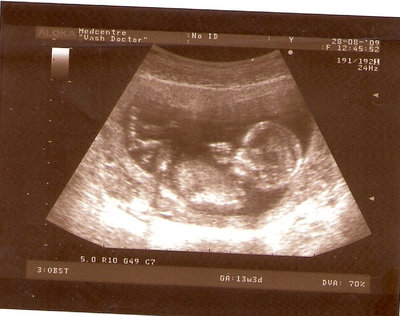

13 НЕД И 5 ДНЕЙ

| Вложения: |

3.jpg [ 96.81 КБ | Просмотров: 2629 ]

Nikisa писал(а): Foto prosto chudesnoe. A na kakom sroke uznali, chto sin.............. НА 13 НЕДЕЛЯХ.КАК РАЗ ВОТ В ЭТО узи, ОНО УМЕНЯ ВТОРОЕ БЫЛО. ЭТО КОНЕЧНО МАЛЕНЬКИЙ СРОК ДЛЯ ОПРЕДЕЛЕНИЯ ПОЛА. НО Я ПОПРОСИЛА ВРАЧА(ЭТО КТСТАТИВ РОССИИ БЫЛО) ХОТЯ БЫ ПРЕДПОЛОЖИТЬ. ЕЙ ВСЁ ТАКИ УДАЛОСЬ РАССМОТРЕТЬ.НУ ВООБЩЕМ ЧЕРЕЗ НЕСКОЛЬ ДНЕЙ ПОЙДУ К ВРАЧУ, УЖЕ АМЕРЕКАНСКОМУ И УЗНАЮ ТОЧНО. К ТОМУ ВРЕМЕНИ У МЕНЯ БУДЕТ СРОК 18 НЕДЕЛЬ. ХОТЕЛОСЬ БЫ ПОСМОТРЕТЬ НА ДРУГИЕ ФОТО НА ЭТОМ СРОКЕ ИЛИ БОЛЬШЕ. ТАК ЧТО ВЫКЛАДЫВАЙТЕ, ЕСЛИ НЕ ЖАЛКО!